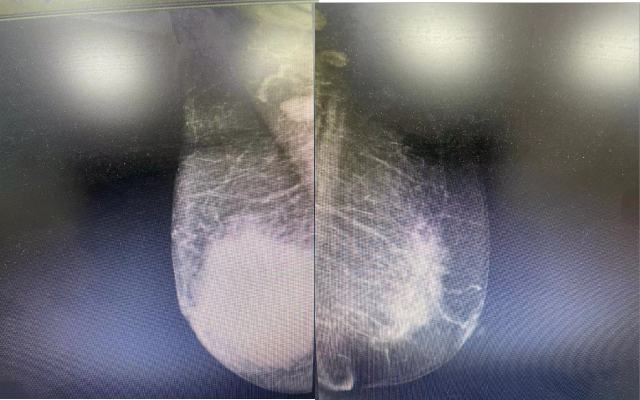

乳腺钼靶片:1 两乳少量型腺体型乳腺;2. 右乳恶性占位,BI-RADS 4c?。

乳腺钼靶片:1 两乳少量型腺体型乳腺;2. 右乳恶性占位,BI-RADS 4c?